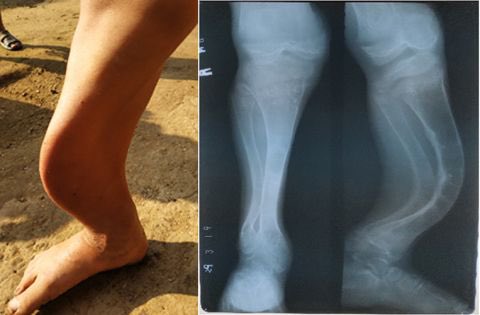

-مهم لبناء عظام صحية🎖🦴

-يساعد على تنظيم مستويات الفوسفات والكالسيوم في الجسم 🏃🏽♂️